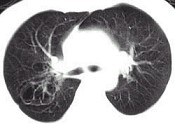

- 单项选择题女,23岁, 咳嗽咳痰反复发作,根据CT图像, 应考虑为 ( )

A、支气管扩张并感染

B、多发肺气囊肿

C、多发性肺囊肿并感染

D、多发性肺脓肿

E、大叶性肺炎